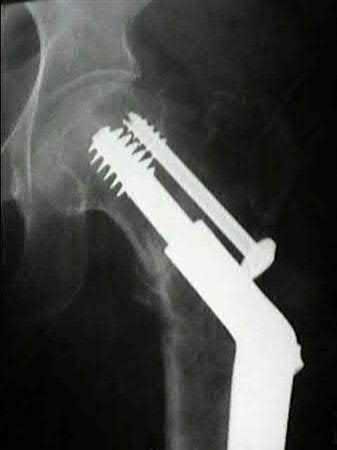

Question 38:

In the treatment of unstable intertrochanteric femur fractures with a cephalomedullary nail, achieving correct lag screw placement is critical. According to the original study by Baumgaertner et al., what is the ideal tip-apex distance (TAD) recommended to minimize the risk of lag screw cut-out?

Options:

- Less than 10 mm

- Less than 15 mm

- Less than 25 mm

- Less than 35 mm

- Greater than 25 mm

Correct Answer: Less than 25 mm

Explanation:

Baumgaertner et al. defined the tip-apex distance (TAD) as the sum of the distance from the tip of the lag screw to the apex of the femoral head on both AP and lateral radiographs, after correcting for magnification. A TAD of less than 25 mm was shown to significantly correlate with a minimal risk of lag screw cut-out in the treatment of intertrochanteric fractures.